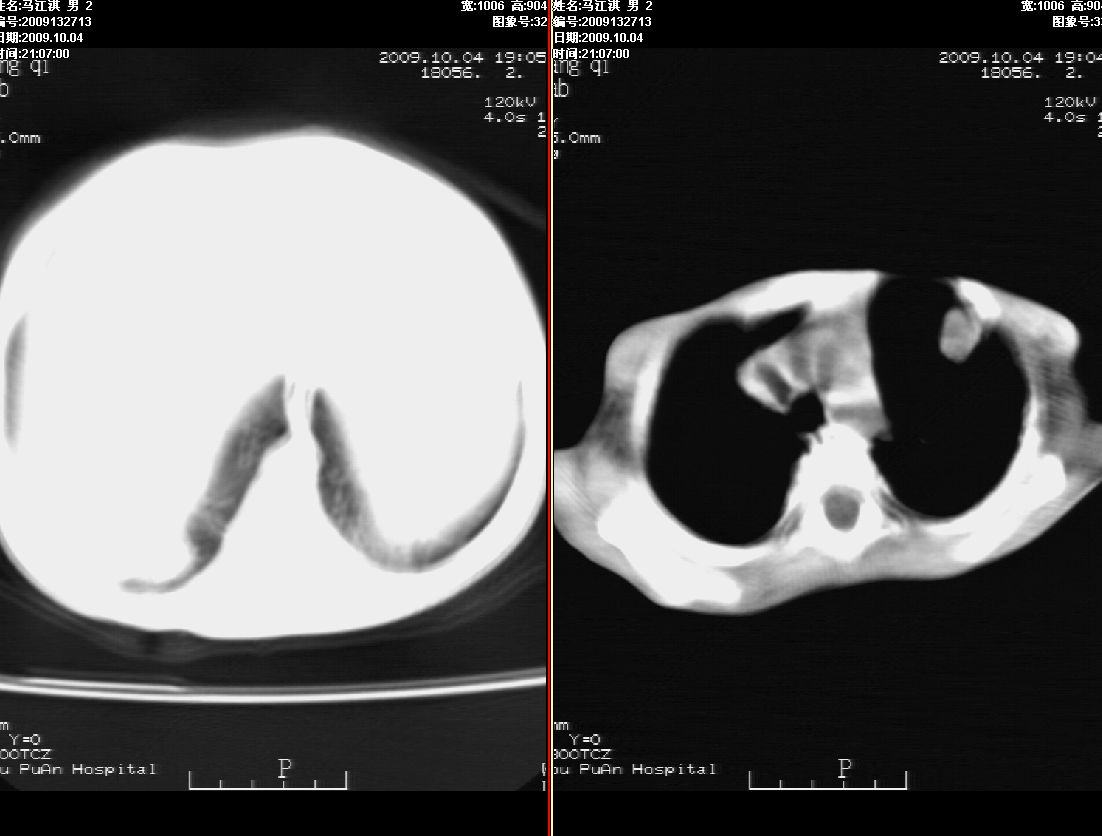

右肾巨大囊性占位病变,其内密度不均,正常肾结构消失,肝脏,肾上腺及肠管等受压移位。双肺内多发大小不等的结节及块状影。考虑右肾母细胞瘤伴双肺多发转移。

肾母细胞瘤(wilms),系儿童最常见的恶性肿瘤,好发于3岁以下儿童,瘤体较大,主要由胚胎性肉瘤样细胞和上皮样细胞构成,临床以腹部肿块;血尿和高血压为主要体征。

ct表现:密度不均匀的大肿块存在;出血和坏死。与神母鉴别点:wilms易向颅脑转移,而神母易往肺转移。

ct表现:密度不均匀的大肿块存在;出血和坏死。与神母鉴别点:wilms易向肺转移。而神母易往颅脑转移.